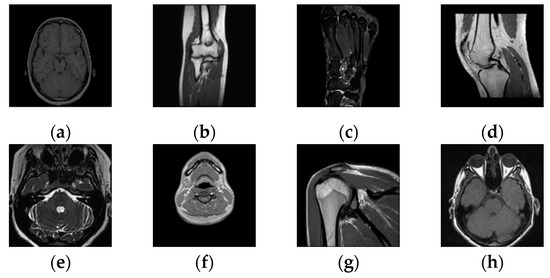

Then, taking this conclusion as a reference, we conducted the same test on a large number of randomly selected medical images, and verified the value of the normalized correlation coefficient between the images using their respective 32-bit symbol vectors. Figure 8 and Table 2 show some of the medical images and the NC values between them. From the data, it can be concluded that the NC values of the different images obtained using the feature vector selected with the above method are all less than 0.5, and their own NC values are 1.00. These results are consistent with human visual features. Therefore, we can take the sequence of coefficient symbols in the low-frequency part of the medical image transformed by DTCWT-DCT as its effective visual feature vector, and correlate the watermarks with it to design the multi-watermarking algorithm.

Figure 8. Some tested images: (a) Brain; (b) Elbow; (c) Foot; (d) Knee; (e) Internal auditory canal; (f) Neck; (g) Shoulder; (h) Orbits.